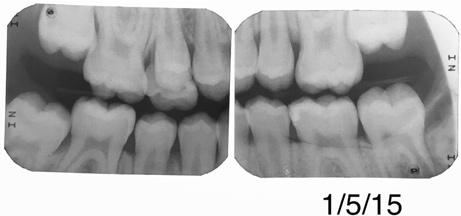

Figure 15 shows bitewings of an 11-year-old boy with high caries risk and history of proximal "kissing lesions" on his primary molars in all four quadrants. He then presented with incipient lesions in his permanent teeth. After resin infiltration (Figure 16), results have been stable for 2 years.

Fig 15. Bitewing of an 11-year-old boy.

Figure 15